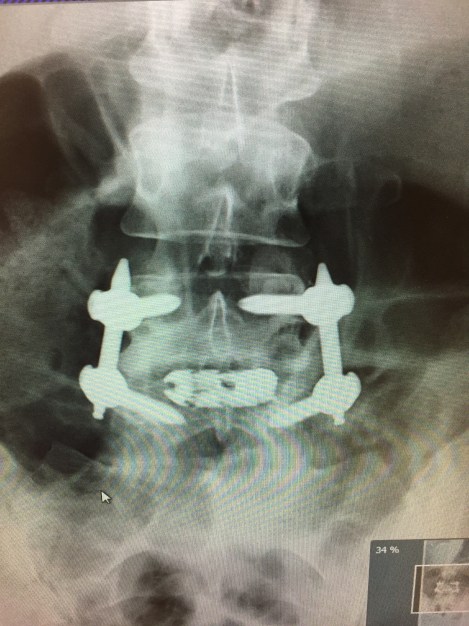

6 months post Lumbar Fusion surgery, was it worth it?

I am now 5 months post spinal fusion. It has been a rollercoaster ride of pain, hope, set backs and frustration, but I really pleased to say that there has been a light at the end of this tunnel. One of the goals all along for me has been to be able to exercise again as I did pre back-pain. Prior to the surgery many people told me that high impact exercise may never be possible again, yet little by little I am coming back.

Just a word of caution. I had fusion L-3 through L-5. I thought things were improving as my surgical trauma was going away and my surgical wounds healed, so I reduced my pain meds. I also returned to my normal activity. As I reduced my pain meds nearly completely, my pain level rose in kind. After 2 years it became apparent that the pain meds kept much of my pain hidden during the 2 years of recovery leading me to conclude (as a neurosurgeon has also) that my return to a normal activity level caused the adjacent joints to further deteriorate and more quickly. I’m back where it all started. I ended up having to increase pain meds again and completely lost my ability to sleep normally. I was facing either another two level fusion or get a neurostimulator implant for the pain, or increase pain meds as the pain increased. I chose the neurostimulator option and though the trial was very good, I am not recovered yet from the implant surgery so I have no relief yet but expect it. So what I am trying to explain is that, like me, you could get a false sense of normality and accelerate inevitable adjacent joint deterioration rather than keeping it at bay indefinitely. My advice from my experience would be to stay active and mobile, but make a very deliberate change in the way you execute your activity. Modify how you do things so as to protect your joints. For example like step around rather than twist, squat to lift instead of bend, use something to assist with weight rather than just dead lifting something, and finally just avoid activity that would put your spinal joints at risk. Best of luck to you.